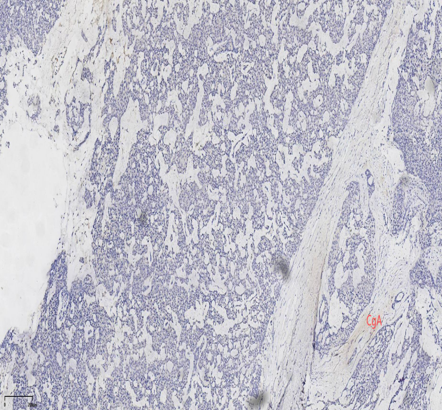

具有神经内分泌表达:CgA、Syn(约70%的比例,阳性细胞表达不等)

CK5/6、CKH-,可斑驳性的残留

肌上皮内-,导管周可-可+